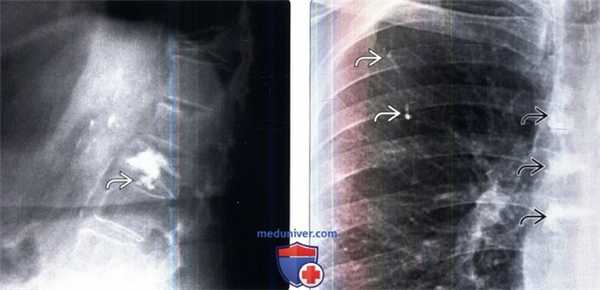

По данным КТ органов грудной клетки от 14.03.13 определяются деструктивные изменения позвонков Th6- 9 с формированием мягкотканного компонента и стенозом данным компонентом позвоночного канала на данном уровне (рисунок № 1). Также определяются множественные метастатические очаги до 0,5 см в обоих лёгких, метастатические очаги в печени.

По данным МРТ пояснично-крестцового отдела позвоночника от 14.09.14 в позвонках Th11-S1 визуализируются множественные метастазы различных размеров (вплоть до тотального поражения позвонка). Данные изменения распространяются на дужку и отростки L1 позвонка с их расширением и деформацией, с выраженным перифокальным отёком паравертебральных мягких тканей и муфтообразным сужением позвоночного канала на данном уровне на 79% — до 0,3 см. Элементы конского хвоста компремированы и деформированы на данном уровне (рисунок № 3).